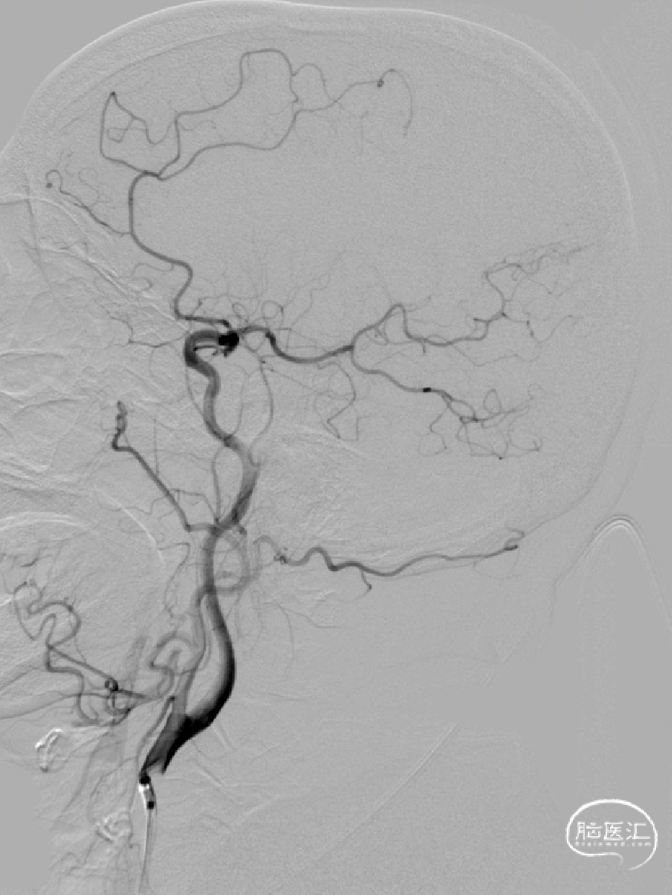

React™ 71远端通路导管到位后行持续负压抽吸。抽吸后造影提示:右侧大脑中动脉血管成功再通。

术后DSA:

右侧大脑中动脉再通,mTICI 3级。